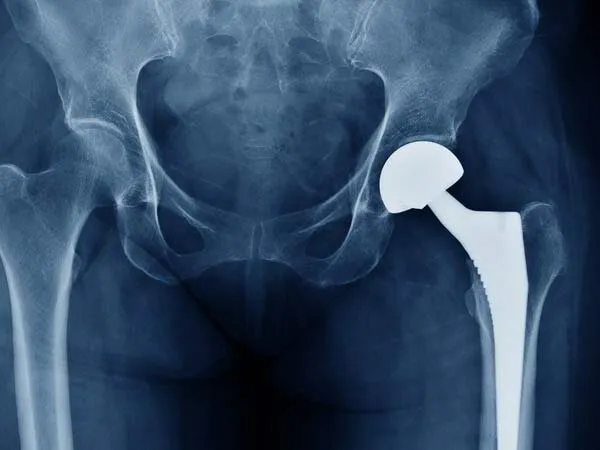

We specialize in Joint Replacement Surgery in Surat, including Knee Replacement, Hip Replacement, and Revision Joint Replacement procedures with modern surgical techniques and personalized patient care.

Dr. Italiya has extensive expertise in trauma care, joint replacement surgeries (knee & hip), fracture management, arthritis treatment, and spine-related conditions. His approach focuses on long-term recovery and functional restoration rather than temporary pain relief.